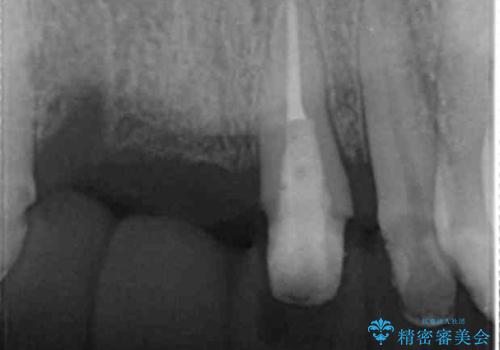

前歯が折れた 前歯部審美セラミックブリッジ治療

- ブリッジの根元が折れ、審美性の改善・治療を求めて来院されました。

保存の難しい歯を抜去しロングブリッジによる補綴を選択しました。

かみ合わせの観点からインプラント治療は難しく、入れ歯も希望されなかったためブリッジによる補綴を選択しました。